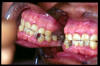

CM El paciente tiene que protuir la mandíbula para poder ocluir